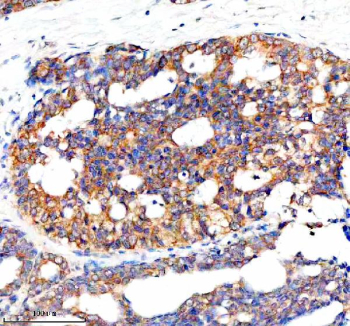

Immunohistochemical staining of NCR3LG1 using anti-NCR3LG1 antibody. NCR3LG1 was detected in a paraffin-embedded section of human breast cancer tissue. Heat mediated antigen retrieval was performed in EDTA buffer (pH 8.0, epitope retrieval solution). The tissue section was blocked with 10% goat serum. The tissue section was then incubated with 2 ug/ml rabbit anti-NCR3LG1 antibody overnight at 4oC. Peroxidase Conjugated Goat Anti-rabbit IgG was used as secondary antibody and incubated for 30 minutes at 37oC. The tissue section was developed using an HRP secondary and DAB substrate.